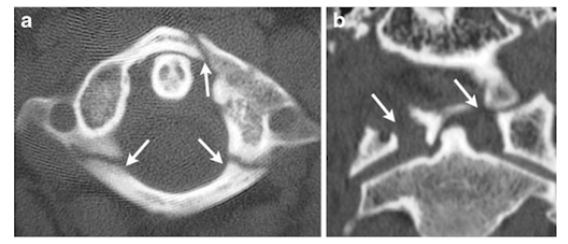

What is the fracture seen in the image below and how is it caused?

JEFFERSON (C1) FRACTURE caused by Axial Load

(Football player spearing another or diving into a shallow pool)

HANGMANS fracture (pedicles of C2) caused by a hyperextension injury

(classically due to hanging)